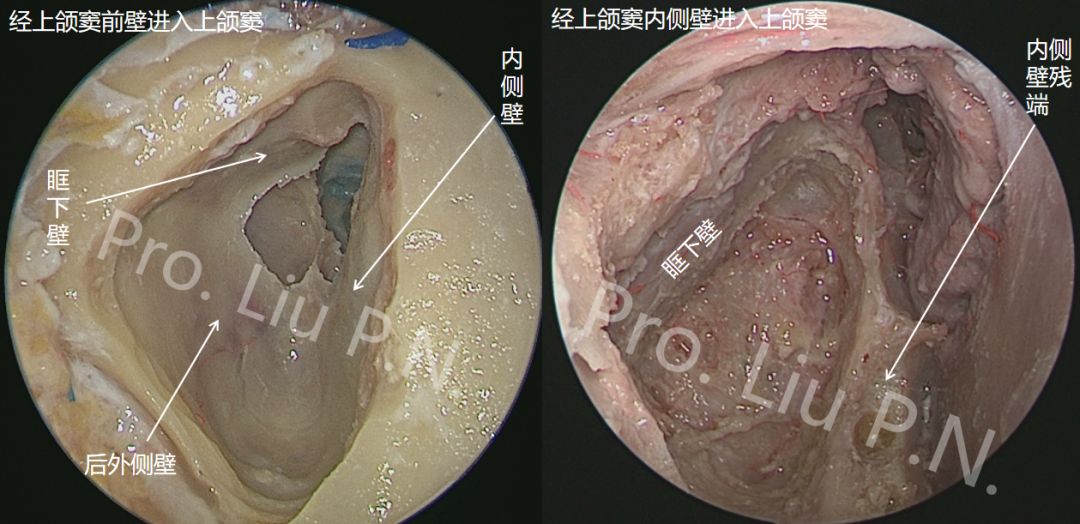

十一、经上颌窦-蝶骨大翼-海绵窦

入路内镜解剖

![]()

内镜进入上颌窦的手术通道不仅限于经鼻腔开放上颌窦内侧壁(经鼻-上颌窦内侧壁入路;泪前隐窝入路),还包括唇下切口开放上颌窦前壁(Caldwell-Luc入路)、经鼻腔梨状孔切口开放部分上颌窦前壁及部分上颌窦内侧壁(Denker’s入路),此外,传统口腔颌面外科常用鼻侧切开方法开放上颌窦前壁进入上颌窦。无论从什么角度进入上颌窦,最终都可以通过切除上颌窦后外侧壁及翼突进入颞下窝,进而进一步显露蝶骨大翼腹侧面、咽鼓管区、上咽旁间隙等区域。不同进入上颌窦的手术通道其器械自由度、显露范围、手术通道路径、及扩展能力略有不同,也都有各自局限性。

切断翼外肌上、下头在翼突外侧板的附着点,外翻翼外肌上、下头,清理肌间隙内静脉丛及骨膜,显露蝶骨大翼腹侧面

去除左侧翼突及蝶骨大翼骨质,显左侧露海绵窦外侧壁、前壁、卵圆孔、颞极、咽鼓管及咽旁间隙